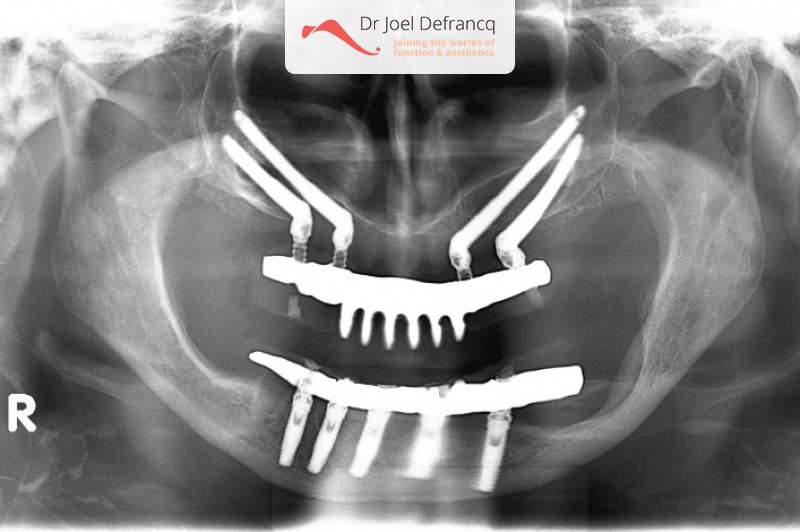

Paula: Dentale implantaten boven en onder / onmiddelijke belasting / Dentale zygoma implantaten

Behandeling tandheelkundige implantaten

- Vaste tanden op implantaten (bovenkaak)

- Vaste tanden op implantaten (onderkaak)

- Zygoma implantaten